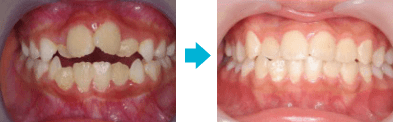

骨切り手術をせずに上顎前突を改善

成人歯列矯正症例